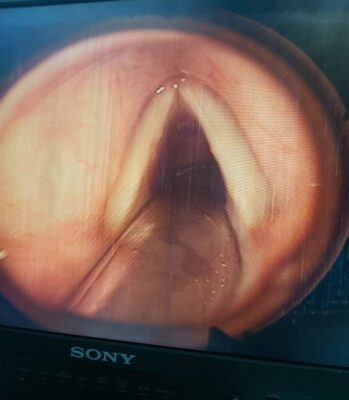

Hình 3: Hạt xơ dây thanh 2 bên

Hạt xơ dây thanh 2 bên trước và sau mổ bệnh nhân Nguyễn Thị N